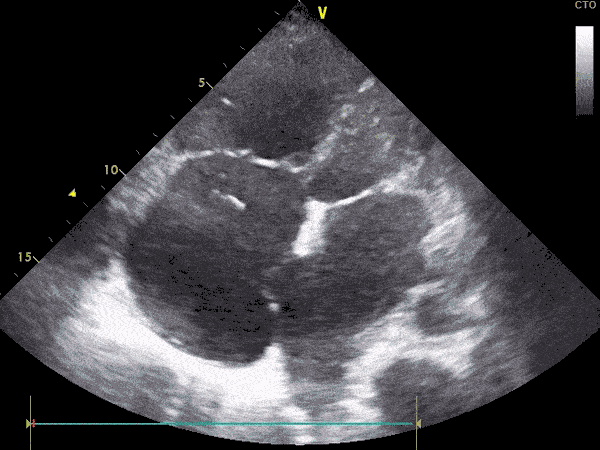

Ekografia kardiake, e njohur edhe si eko e zemrës, është një ekzaminim imazherik që përdor valët me ultratinguj për të krijuar pamje në kohë reale të zemrës. Ajo përdoret gjerësisht për të vlerësuar strukturën dhe funksionin e zemrës, pa përdorur rrezatim.

Gjatë ekografisë kardiake, mjeku përdor një sondë që transmeton valë zanore dhe krijon imazhe të detajuara të zemrës në lëvizje.

Ky ekzaminim lejon vlerësimin e:

• Madhësisë dhe formës së zemrës.

• Funksionit të muskulit kardiak.

• Valvulave të zemrës.

• Qarkullimit të gjakut brenda zemrës.

• Pranisë së lëngut rreth zemrës.

Në varësi të nevojës, ekografia mund të shoqërohet edhe me Doppler, për të analizuar rrjedhën e gjakut nëpër valvula dhe enë.